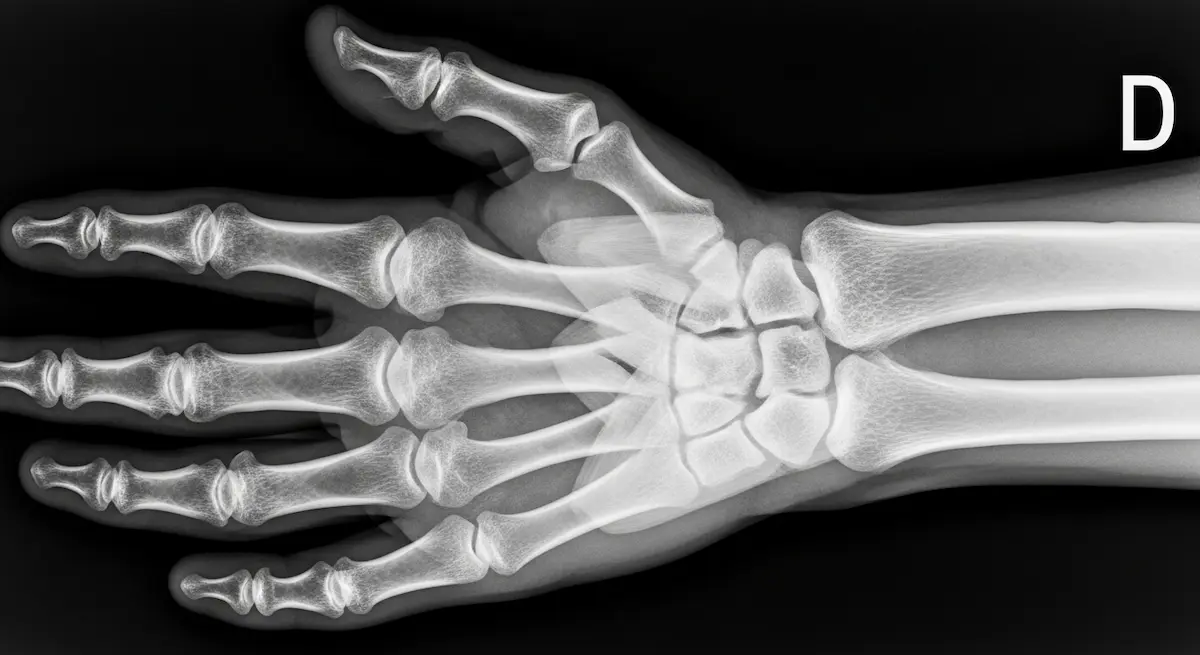

Como cirurgião especialista em cirurgias minimamente invasivas da mão e punho, uma das perguntas mais frequentes que recebo dos meus pacientes é: quanto tempo de recuperação da cirurgia no dedo da mão é necessário para retomar as atividades normais? Essa…